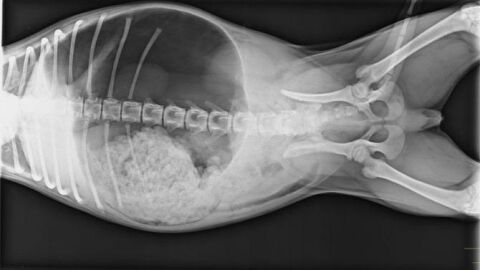

Veterinario de Cabecera 06/02/2024 (Dilatación-torsión de estomago en perros)

Afecta a razas de gran tamaño y la solución suele ser quirúrgica